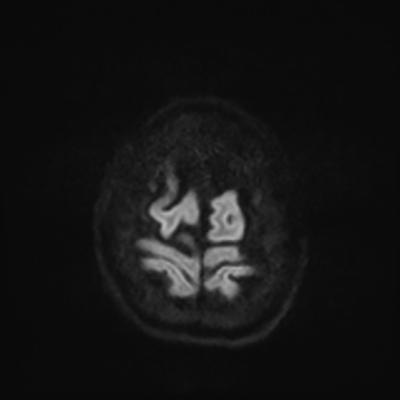

MRI brain (DWI)

You can clearly see diffuse cortical and basal ganglia diffusion restriction, and that of his deep cerebellar nuclei as well. The right occipital lobe abnormalities are a little more prominent, but then you remember that he is known to have had a right occipital stroke weeks ago.

In reviewing his data, you know that he doesn't have any of the strong predictors of a poor neurologic prognosis. However, based on these findings on MRI, along with the absent reactivity on cEEG, you are able to tell the primary team and the patient's family that he is likely to have a poor prognosis, based on these multiple moderate predictors. Recovery is not completely impossible-- there is more uncertainty with this prognostication than if we were able to get SSEPs-- but you're very worried about his outlook and that any potential recovery would require a very protracted rehabilitation period. Given his high cervical cord injury level, tracheostomy would be required anyway. So, it comes down to whether his family thinks he'd want to pursue these aggressive measures.